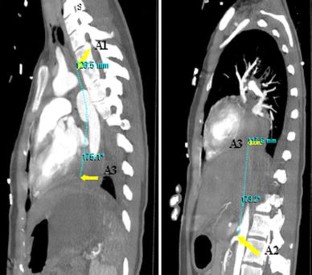

Fig. 2